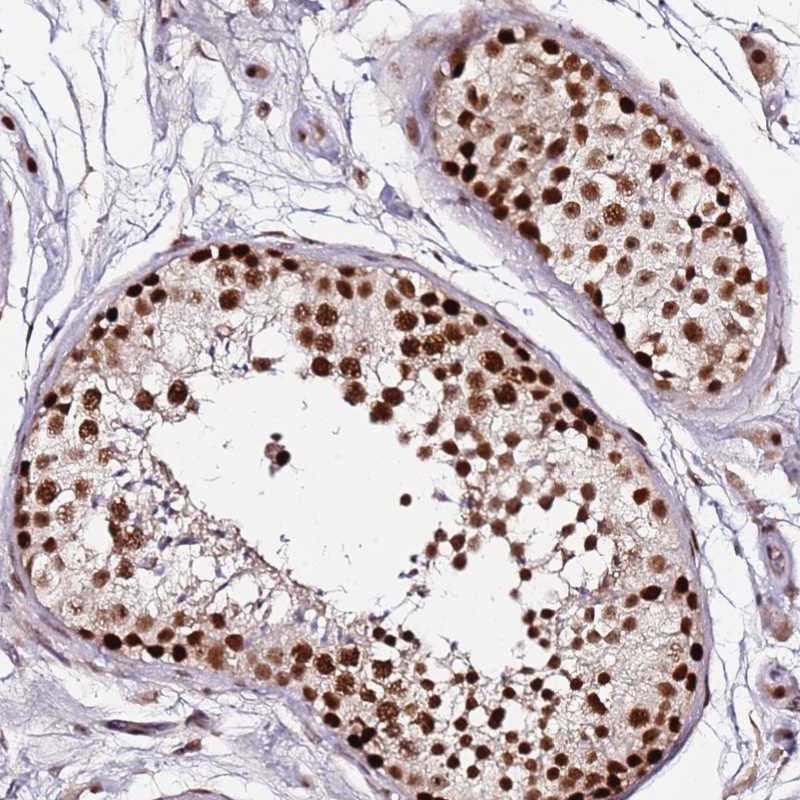

Immunohistochemical staining of human testis shows strong nuclear positivity in cells in seminiferus ducts.